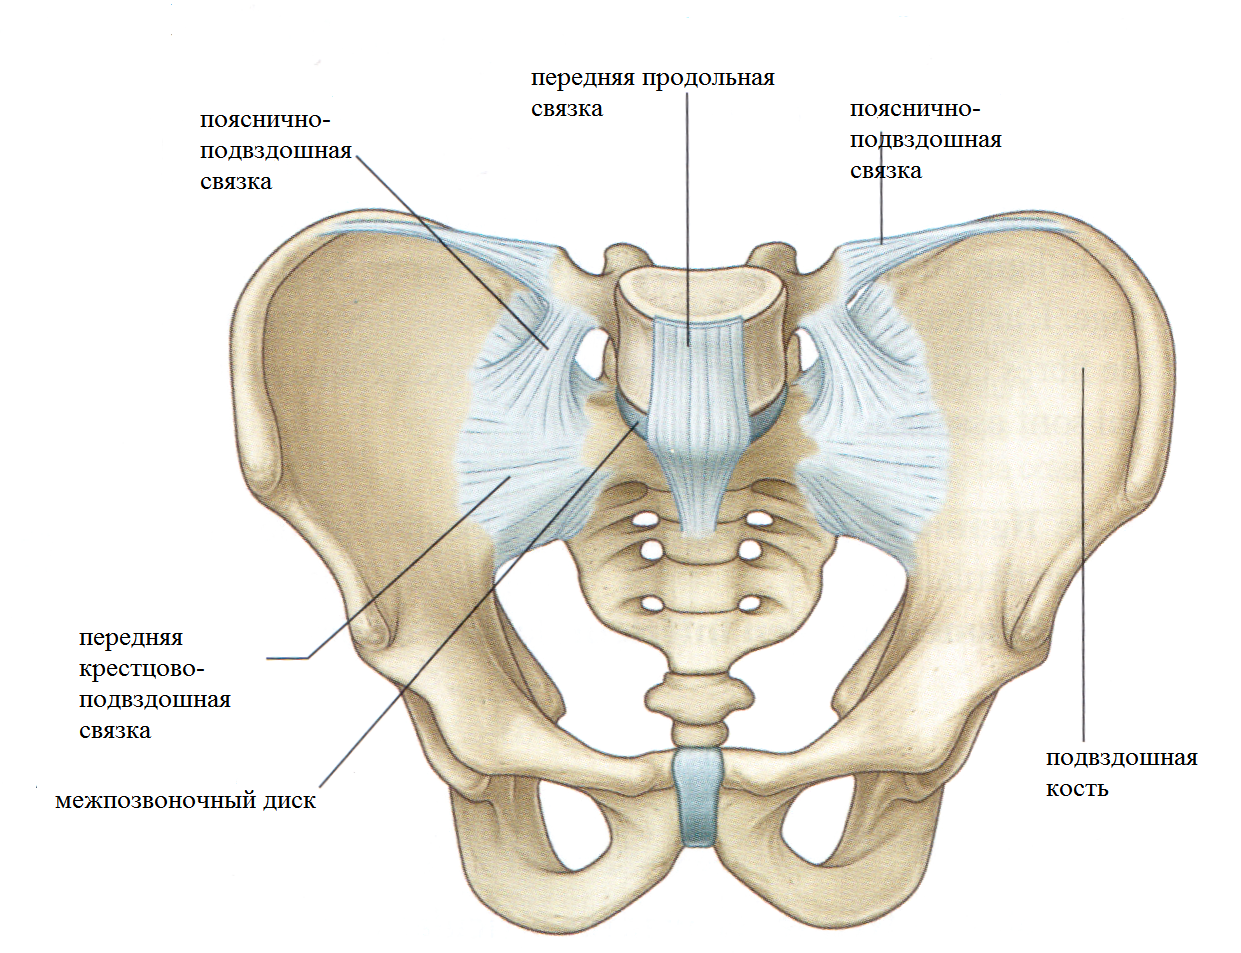

Структура позвоночника: сегменты и тазовые отделы в фотографиях